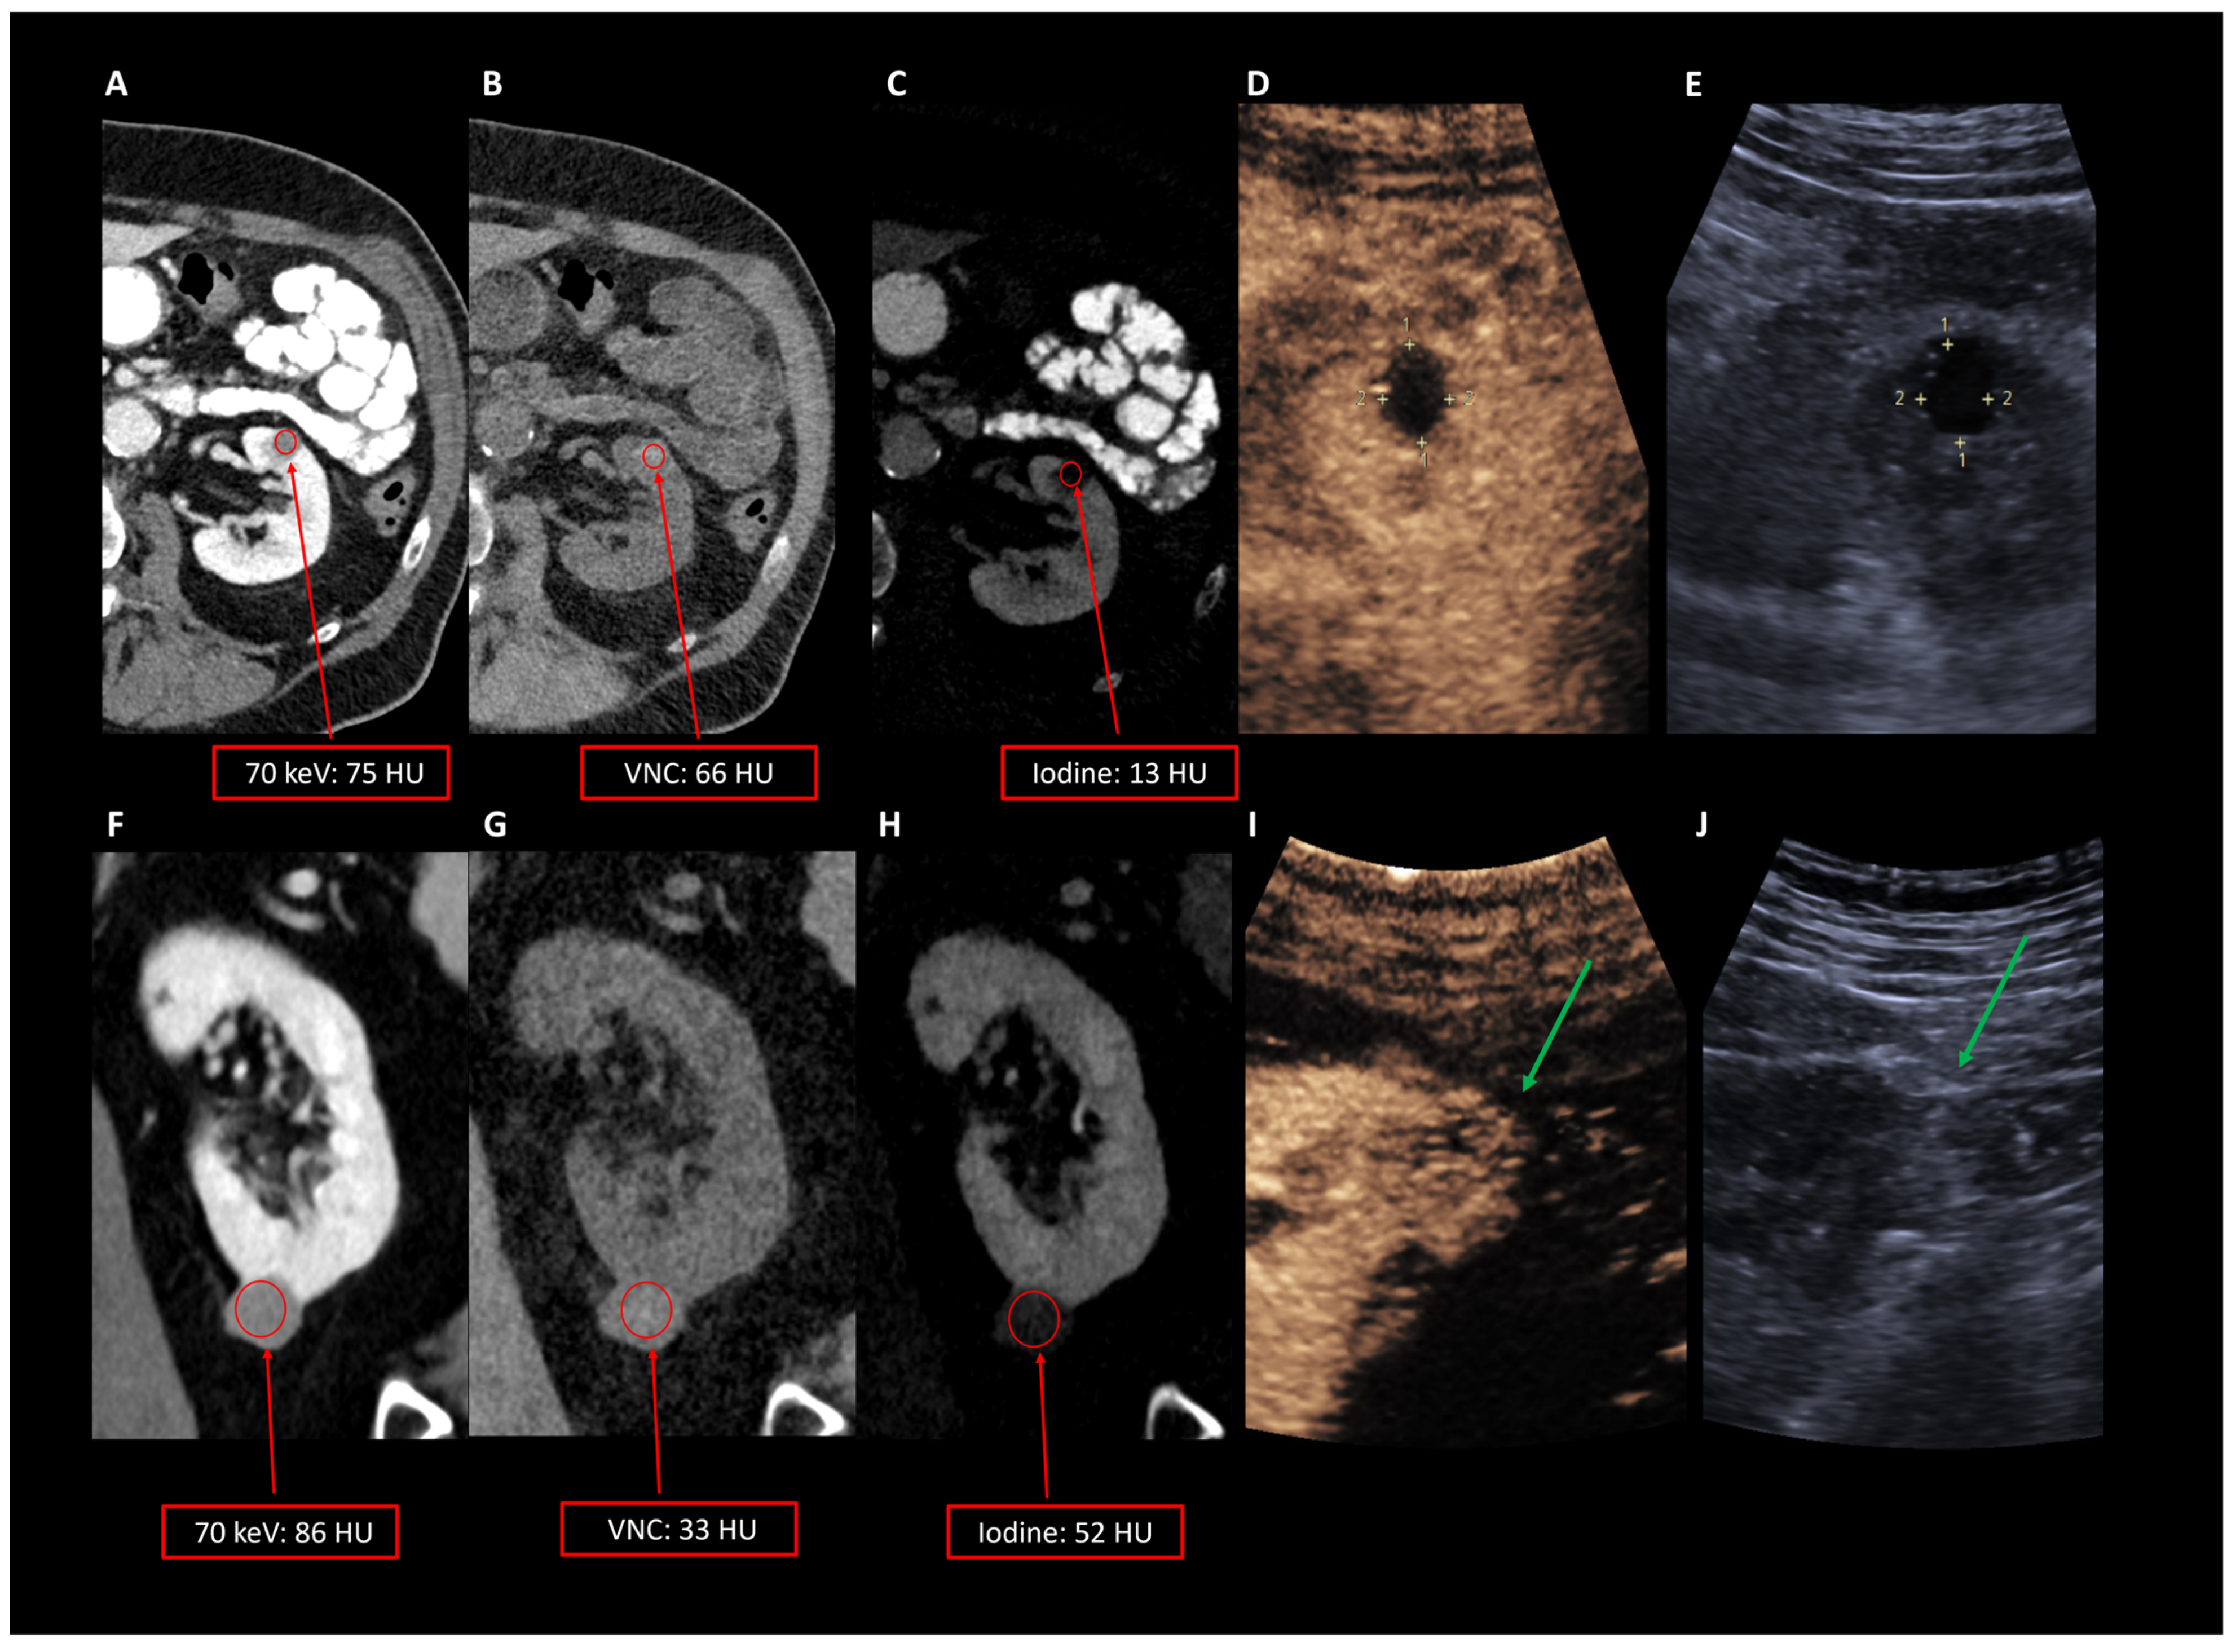

| 70 keV | 64.8 (44.5–73.1) 61.4 (±19.4) | 68.5 (58.0–78.5) 65.5 (±17.4) | 1.000 |

| Iodine maps | 56.2 (35.6–72.7) 55.7 (±24.2) | 31.8 (25.8–38.3) 32.2 (±11.1) | 0.034 |

| VNC | 1.7 (0.0–8.0) 5.7 (±7.8) | 30.3 (25.1–49.0) 33.3 (±19.0) | 0.002 |

| Threshold (HU) | Specificity | Sensitivity | Accuracy |

| Iodine maps | |||

| 20.3 | 0.882 | 0.875 | 0.881 |

| VNC | |||

| 52.0 | 0.559 | 1.000 | 0.643 |

| 70 keV | |||

| 74.0 | 0.500 | 0.765 | 0.714 |